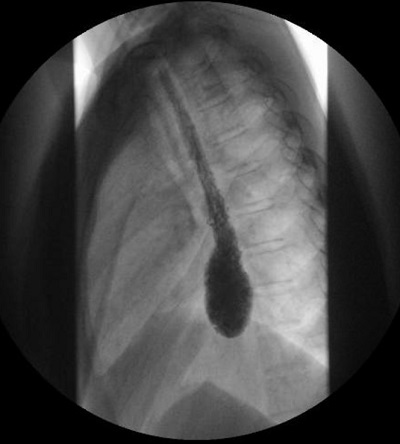

• Tránsito digestivo con contraste baritado (Fig. 1): “dilatación del bolsón distal esofágico con retención de alimentos. No hay paso de contraste a través de la unión esofagogástrica. Conclusión: los hallazgos radiológicos son compatibles con el diagnóstico de acalasia”.

Figura 1. Esofagograma con contraste: dilatación del bolsón distal esofágico con retención de alimentos. No hay paso de contraste a través de la unión esofagogástrica

• Esofagograma con contraste: podemos ver un esófago proximal dilatado sin contracciones peristálticas y con un estrechamiento en la unión esofagogástrica con mínimo o nulo paso de contraste al estómago a modo de “pico de pájaro”2.